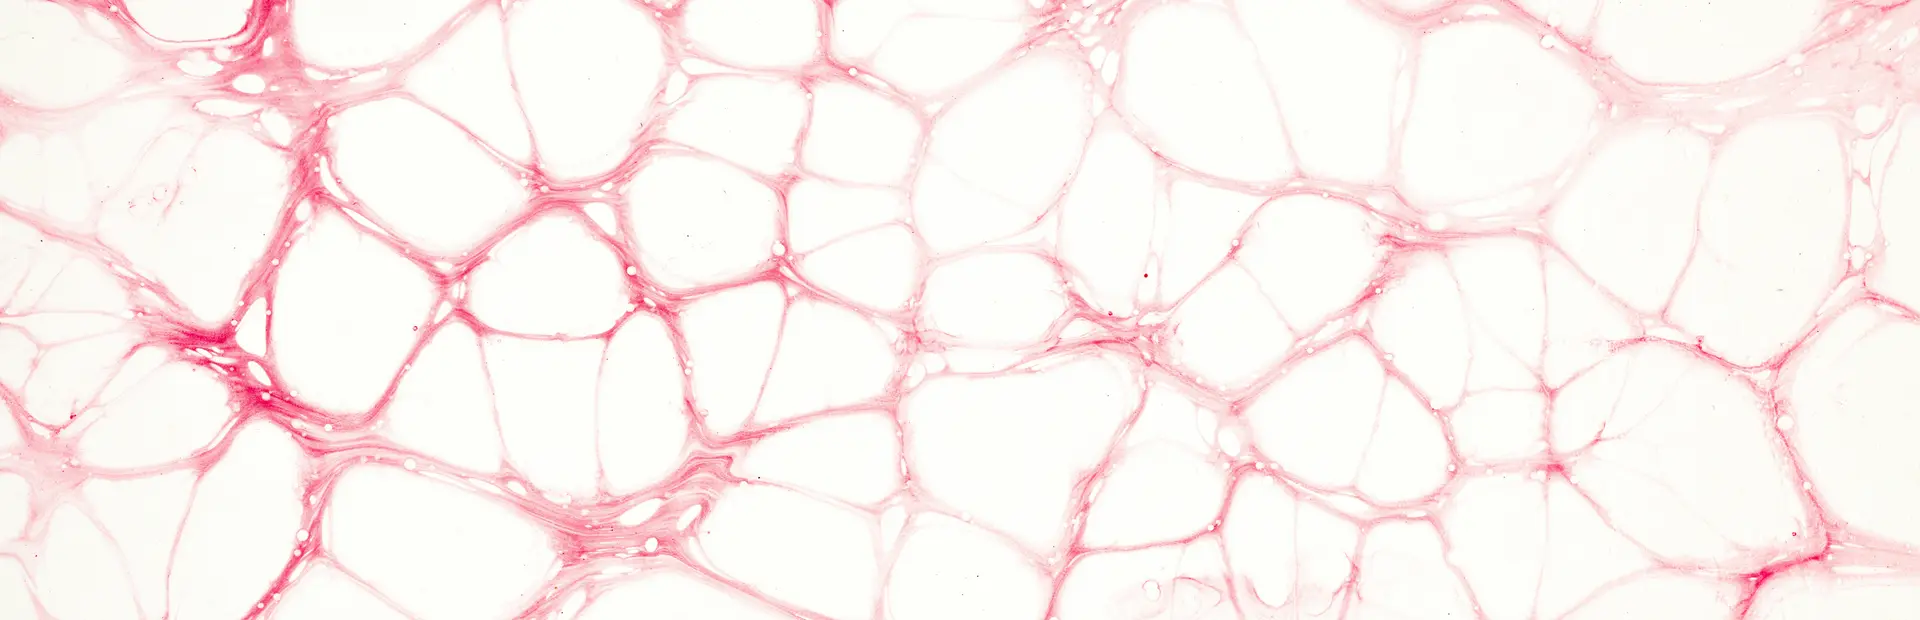

Los TNE comprenden un gran grupo de tumores muy variables que se originan a partir de células neuroendocrinas. Estos pueden aparecer en prácticamente cualquier órgano del cuerpo, aunque las localizaciones más frecuentes son el tubo digestivo, el páncreas y el pulmón.